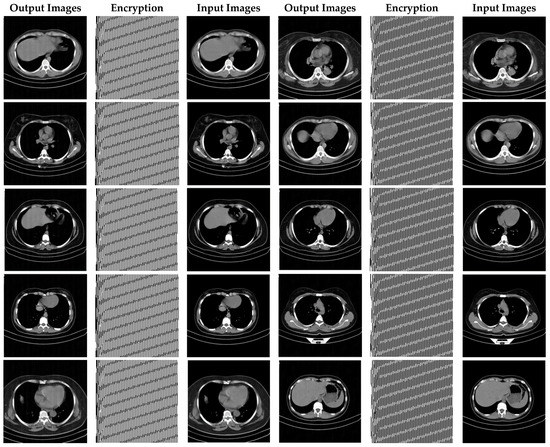

Figure 16.

CT images encrypted using the proposed method.

In Figure 15, X-ray images of patients with COVID-19 for cryptography are exploited. According to Figure 13, it can be seen that the synchronization method of the proposed chaotic system also achieves highly successful outcomes in X-ray images encryption.

Figure 16 demonstrates the various CT encrypted images. According to the figure, the CT images are first fed to the input of the proposed chaotic synchronization method. CT images encrypted are then generated. Finally, reconstructed CT images are represented. According to Figure 16, it can be seen that the cryptographic procedure based on synchronization of the proposed chaotic system achieves successful results.

As can be observed in Figure 16, the recommended method has also been very successful in CT images encryption of people with COVID-19. Additionally, with a conclusion, it is perceived that the cryptographic method based on synchronization of chaotic systems presented in this paper for various medical images and standard benchmarks achieves satisfactory results.